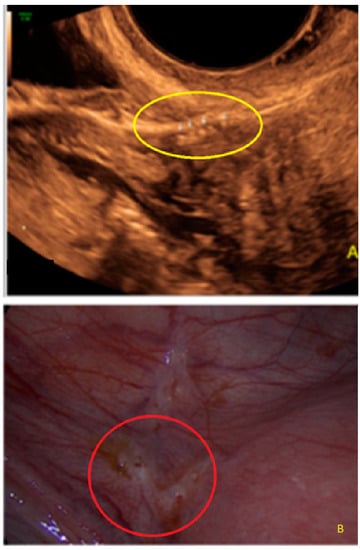

- The lesion may be convex, protruding from the peritoneal surface into the peritoneal cavity (we called this “bulging”), or it may appear as a concave defect in the peritoneum (we called this a “pocket”).

3.1. Cystic Solitary Lesion